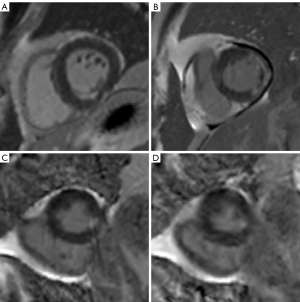

The overall IQ scores of the FLASH PSIR, moco bSSFP, and TrueFISP PSIR for all patients were 3.45 (3.07, 3.64), 3.89 (3.8, 3.91), and 3.91 (3.82, 4), respectively. The overall IQ score for moco bSSFP and TrueFISP PSIR was significantly higher than turbo FLASH (P<0.001). The overall IQ score of moco bSSFP was significantly higher than that of TrueFISP PSIR (P<0.001). The LGE image of a typical patient is illustrated in Figure 3. To further investigate the differences in overall IQ scores of the three LGE sequences between the three groups, we performed a subgroup analysis. The same results were finally obtained, as detailed in Figure 4.

Arrhythmia had a negative impact on IQ scores on FLASH PSIR, resulting in poor or non-diagnostic IQ in 4 patients. IQ score was not influenced by arrhythmia in the two fast sequences.